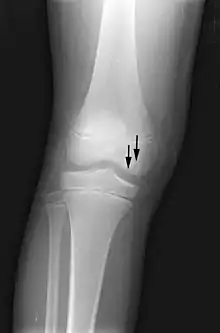

X-ray images of avascular necrosis in the early stages usually appear normal. In later stages it appears relatively more radio-opaque due to the nearby living bone becoming resorbed secondary to reactive hyperemia.[2] The necrotic bone itself does not show increased radiographic opacity, as dead bone cannot undergo bone resorption which is carried out by living osteoclasts.[2] Late radiographic signs also include a radiolucency area following the collapse of subchondral bone (crescent sign) and ringed regions of radiodensity resulting from saponification and calcification of marrow fat following medullary infarcts.

The intravertebral vacuum cleft sign (at white arrow) is a sign of avascular necrosis. Avascular necrosis of a vertebral body after a vertebral compression fracture is called Kümmel's disease.[17]